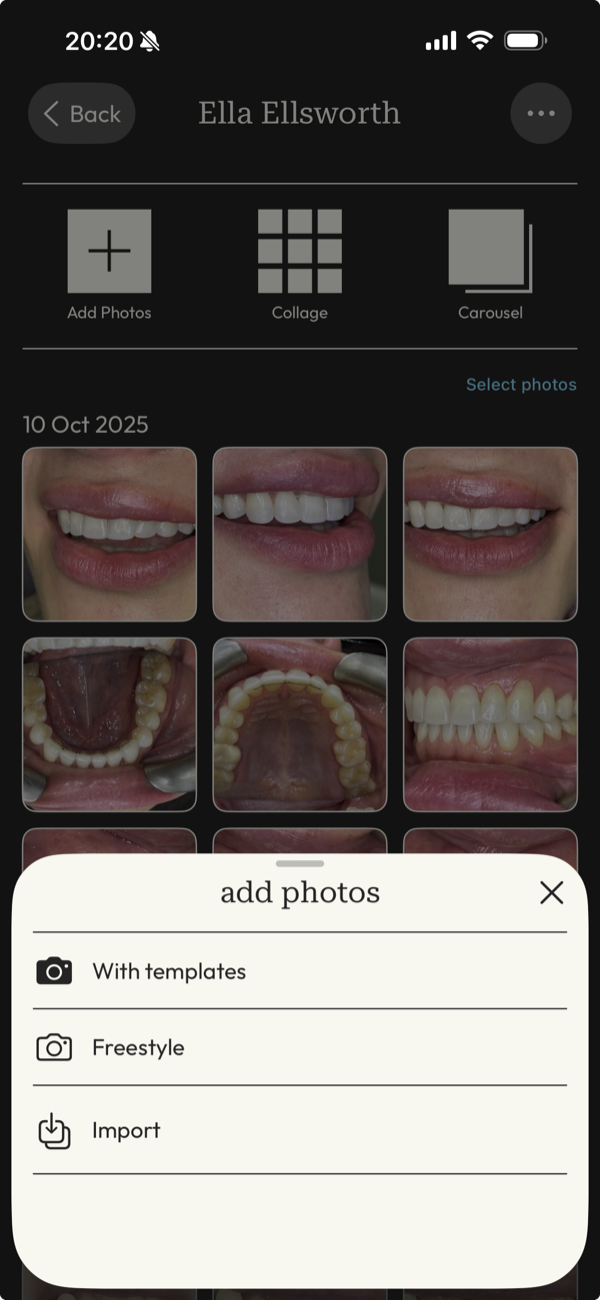

picture perfect images

Capture images with guided precision or import your DSLR work, then transform them into flawless before-and-after cases ready to present and share.

all your photos in one place

Manage your portfolio effortlessly from your phone, and sync with other devices for optimised, up-to-date images, organized by patient and date.

DentalFolio is designed around how clinical photography is actually used: by patient, by case, and for clear before-and-after presentation, with consent information kept alongside the images.

The real time sink is finding the right images when they're needed, often just before or during a patient conversation. DentalFolio keeps photos organised by patient and case, removing the need to scroll through unrelated images.

Photos captured in the app are also automatically oriented, reducing small points of friction that add up over time. The result is a calmer chairside experience with fewer interruptions to flow.